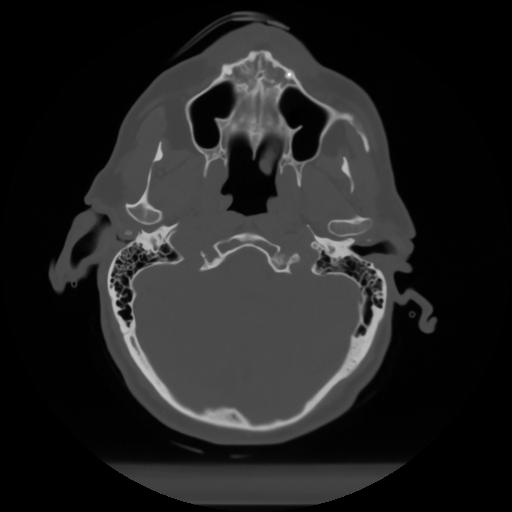

10 P.BLANDAS,,Axial,2.0,P.BLANDAS,,